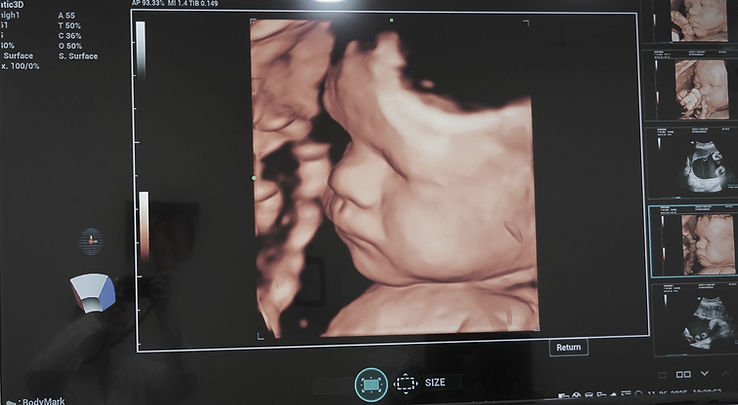

Real-time insight into your health.Ultrasound (USG) is a non-invasive imaging method that uses sound waves to provide detailed images of internal organs, tissues, and blood flow — with no radiation exposure. It’s one of the most trusted diagnostic tools in modern medicine.Our radiology department offers advanced diagnostic imaging with a strong emphasis on early detection, clinical accuracy, and patient comfort. Using state-of-the-art, high-resolution ultrasound equipment, we provide detailed examinations of the thyroid glands, abdominal organs, breasts, pelvic structures, musculoskeletal regions, and vascular systems. These services are available for both adults and children, supporting the diagnosis of a wide range of conditions, from organ abnormalities and inflammatory processes to congenital issues and soft tissue injuries. Pediatric ultrasound is performed with extra care and adapted techniques to ensure safety, precision, and minimal stress for our youngest patients.Our ultrasound capabilities play a critical role in detecting conditions such as gallstones, liver disease, uterine fibroids, ovarian cysts, and vascular anomalies. Specialized gynecologic and transvaginal scans further support reproductive and oncological evaluations with high diagnostic accuracy.For expectant parents, GI Rimon Med proudly offers 4D ultrasound technology, providing real-time, moving views of the baby in utero. These advanced scans support prenatal screening through detailed fetal anomaly assessments, facial structure imaging, and movement monitoring. The 4D experience enhances both medical precision and emotional connection, offering memorable insights during pregnancy. Whether used for pediatric care, general diagnostics, or prenatal monitoring, our ultrasound services reflect the clinic’s commitment to comprehensive, family-centered, and technologically advanced care.

3D/4D imaging (on request)